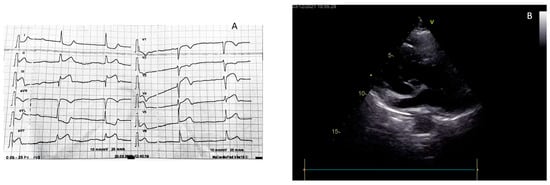

| Papillary muscle rupture and acute mitral regurgitation |

| Ventricular septal defect |

| Rupture of the ventricular free wall |

| Pseudoaneurysm |

| Left ventricular apex thrombosis |